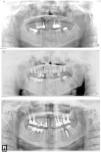

Los estudios prospectivos sobre la tasa de éxito de los implantes insertados en alvéolos con infección periapical previa no indican mayor índice de complicaciones y recomiendan este tipo de procedimiento en las condiciones del correcto desbridamiento alveolar. Este aspecto va en contra de las suposiciones iniciales sobre la etiología, que presentaban la lesión alveolar previa como un factor etiológico importante20,21. En la serie presentamos un caso de reaparición de la lesión apical previa (el caso número 6), el único caso de la serie que tiene efectuado el examen anatomopatológico (resultado compatible con quiste periapical) (fig. 2 a, b, c).

a) Caso número 6: radiografía preoperatoria que muestra lesión periapical quística a nivel del incisivo lateral superior derecho. Se realizó exodoncia del diente 12 y legrado del área apical con buena cicatrización. b) Vuelve a aparecer el área periapical después de la inserción del implante que presenta buena estabilidad; se realizó curetaje. c) Resultado final después de cirugía periapical asociada con relleno óseo.

La resección del ápice implantario generalmente se recomienda en casos en los que impide la completa eliminación del tejido de granulación, o cuando están localizados en seno maxilar o cavidad nasal26 (fig. 3 a,b).

a) Caso número 4: presencia de zona radiolúcida alrededor del ápice implantario del implante mandibular más posterior. En este caso la inserción implantaria se realizó a la vez que la lateralización del nervio alveolar inferior derecho. b) Control radiológico después de cirugía periapical sin relleno óseo. La resección del ápice fue necesaria para acceder correctamente a toda la zona de osteítis.